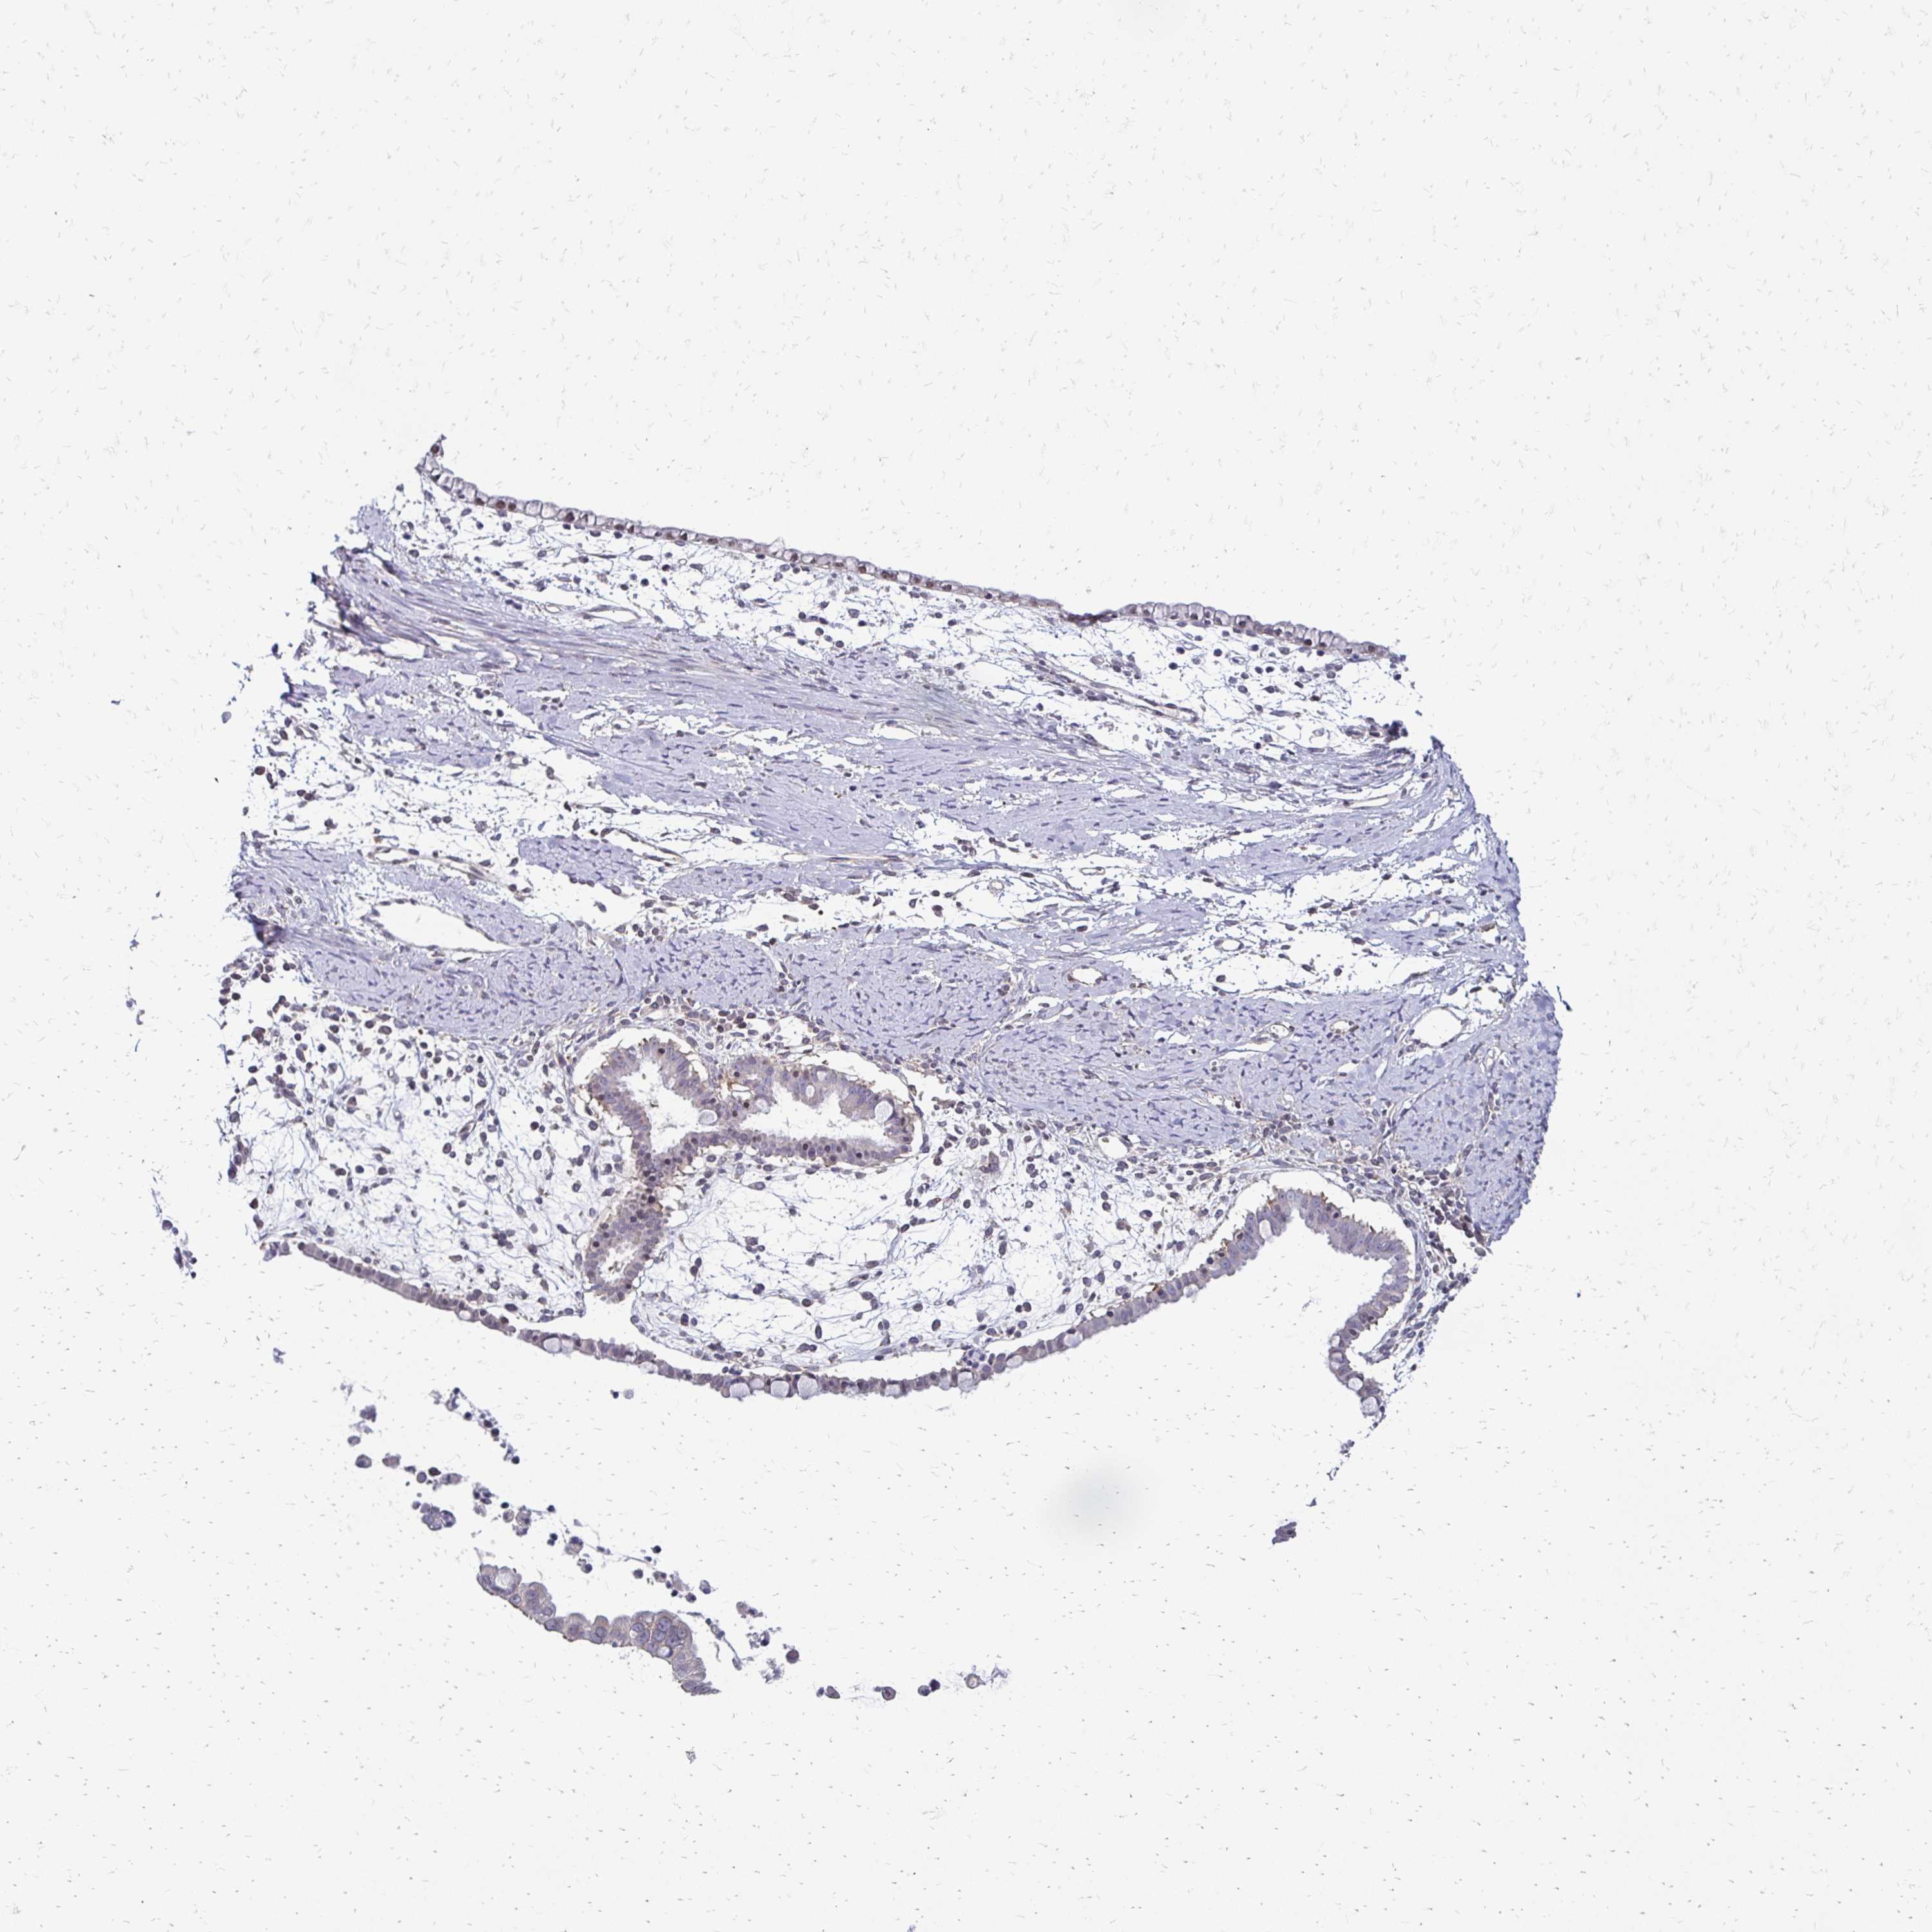

OVARIAN CANCER - Protein expressioni

A mouse-over function shows sample information and annotation data. Click on an image to view it in a full screen mode. Samples can be filtered based on level of antibody staining by selecting one or several of the following categories: high, medium, low and not detected. The assay and annotation is described here.

Note that samples used for immunohistochemistry by the Human Protein Atlas do not correspond to samples in the TCGA dataset.

Antibody stainingi

Antibody staining in the annotated cell types in the current human tissue is reported as not detected, low, medium, or high, based on conventional immunohistochemistry profiling in selected tissues. This score is based on the combination of the staining intensity and fraction of stained cells.

Each image is clickable and will lead to virtual microscopy that enables deeper exploration of all samples and also displays staining intensity scores, fraction scores and subcellular localization as well as patient and tissue information for each sample.

Antibody HPA048677

Antibody HPA056480

Antibody CAB011574